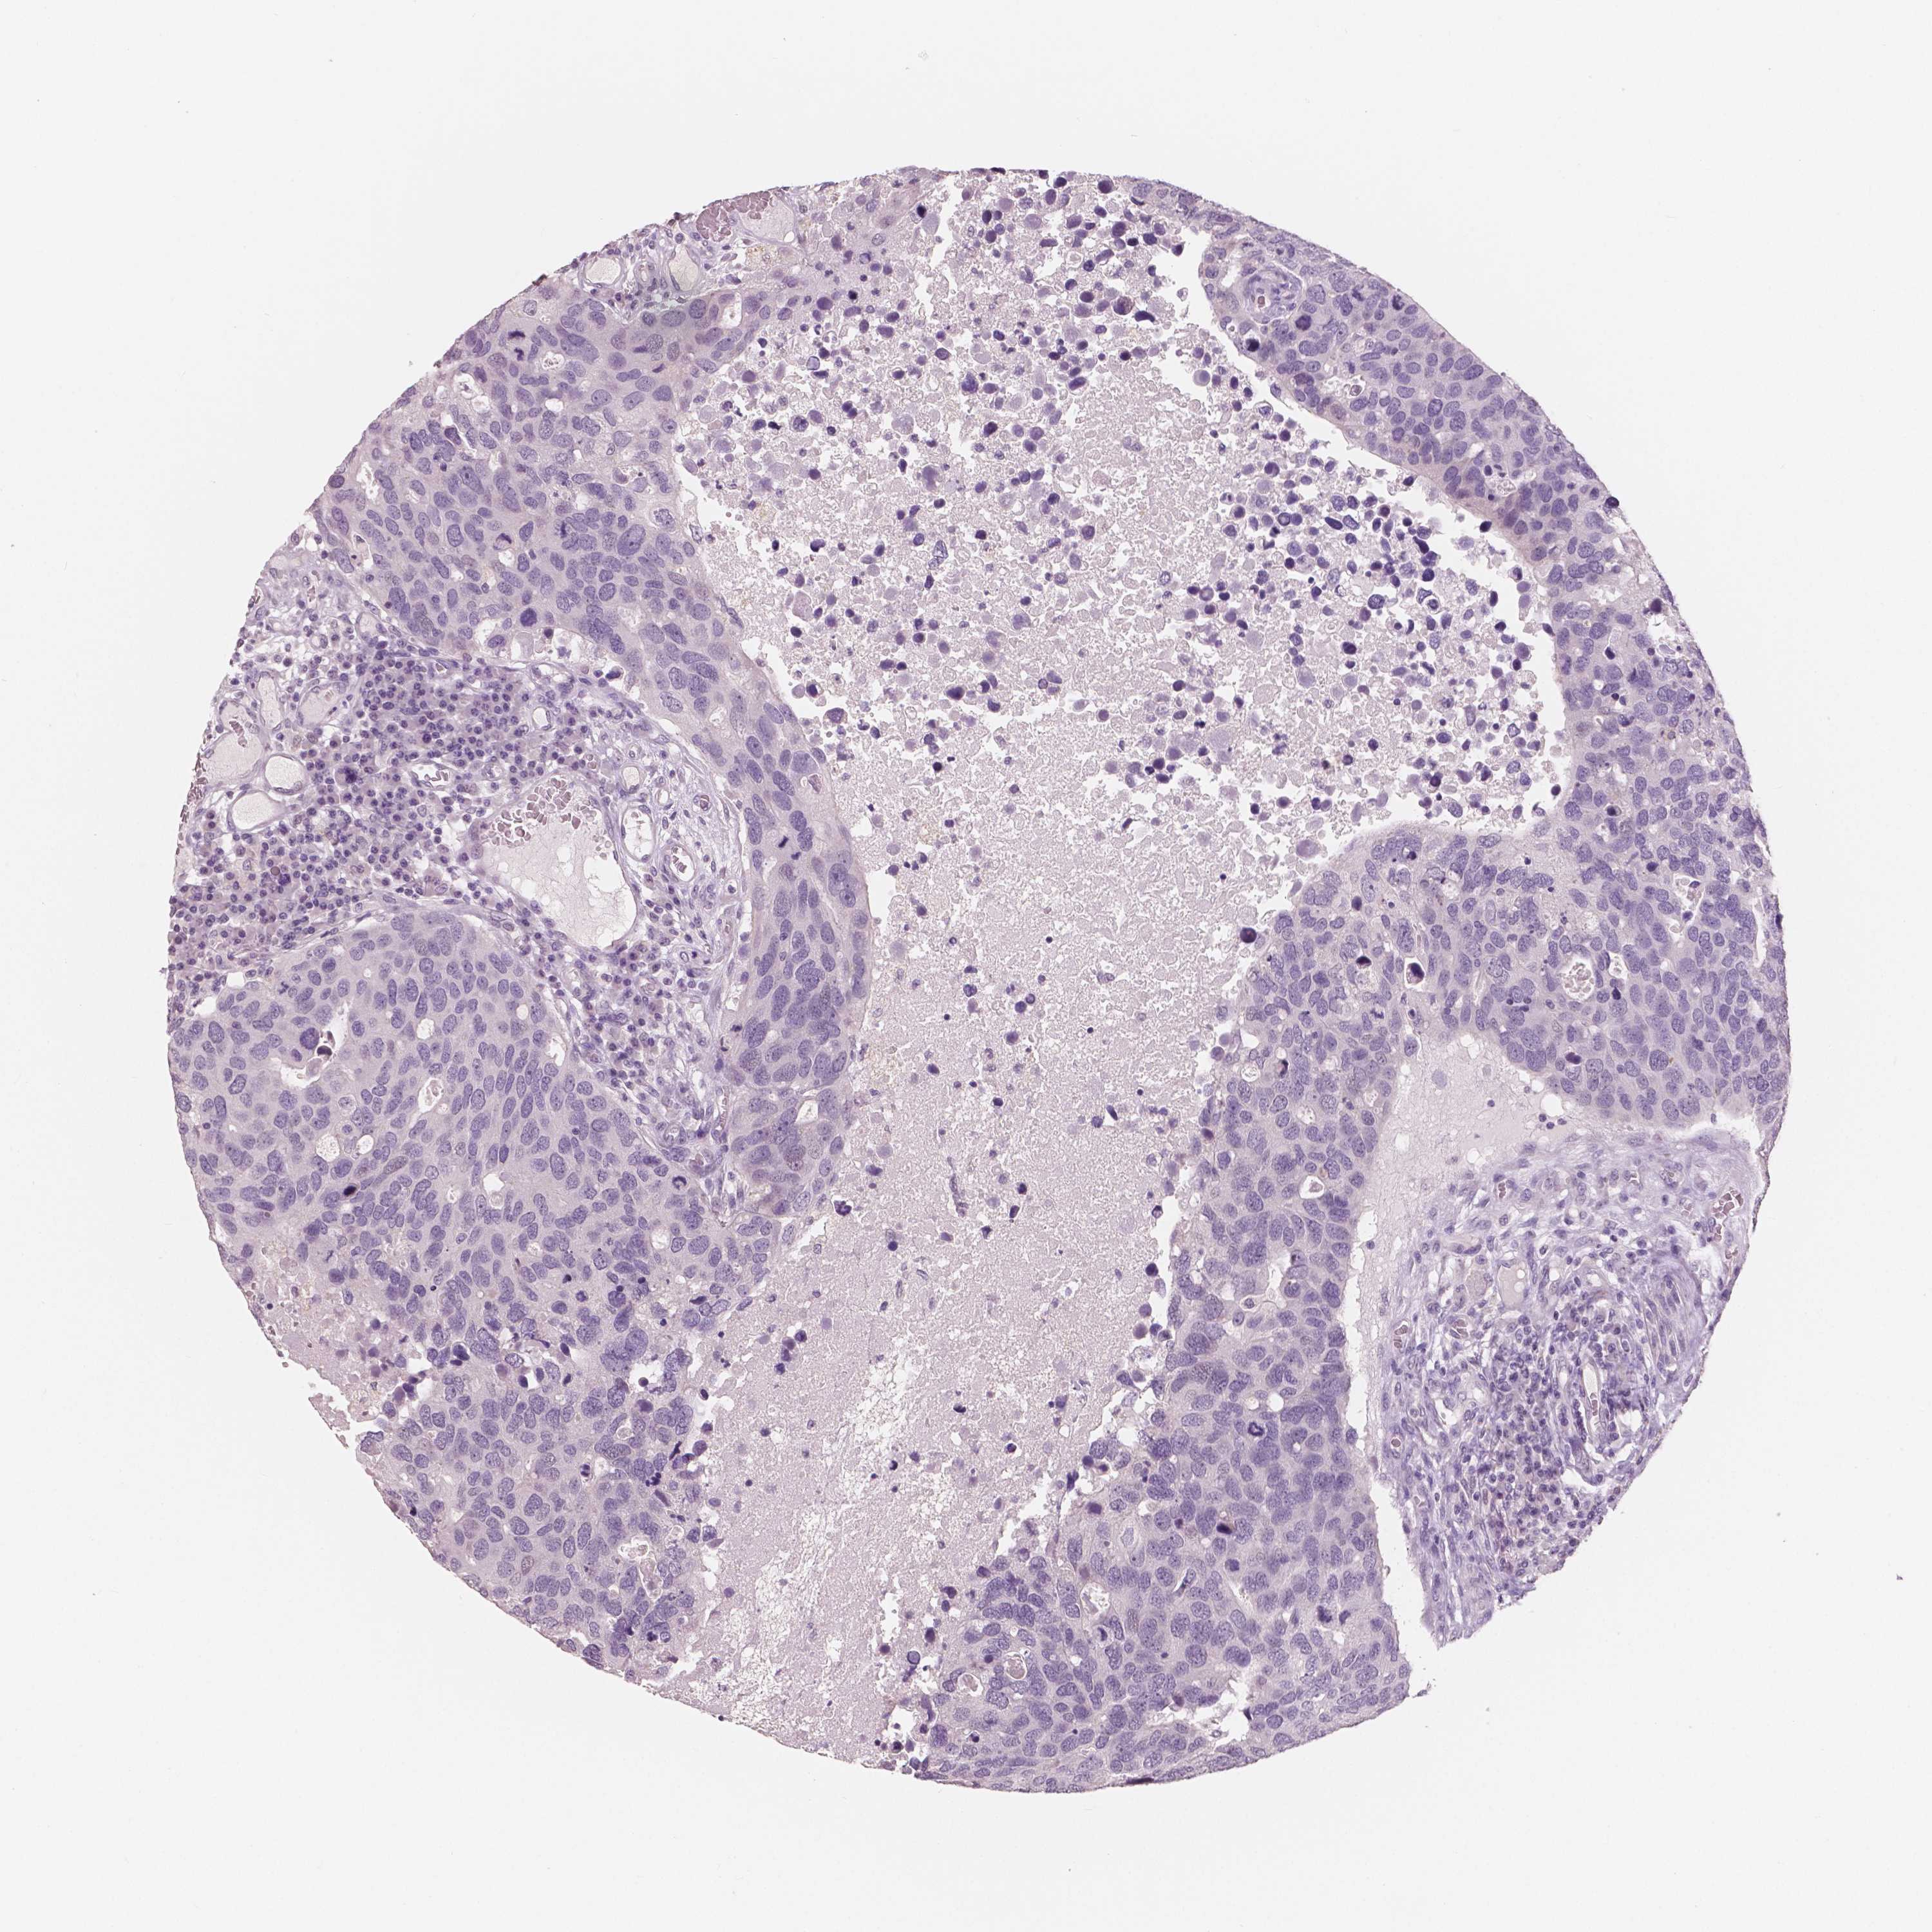

Breast cancer

Human cancer